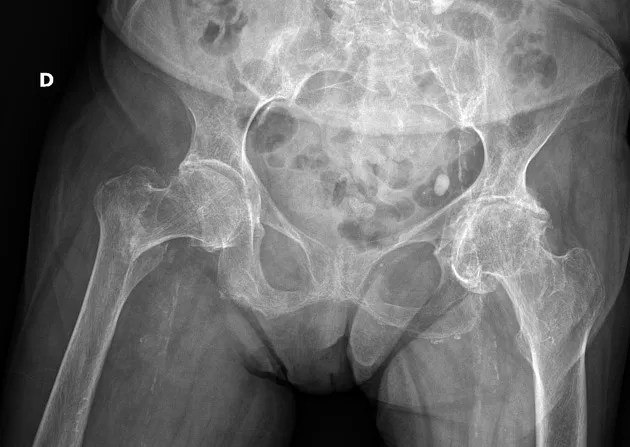

What is seen in this image?

{{c1::Right neck of femur fracture}}

Case courtesy of Leonardo Lustosa, Radiopaedia.org. From the case rID: 98970